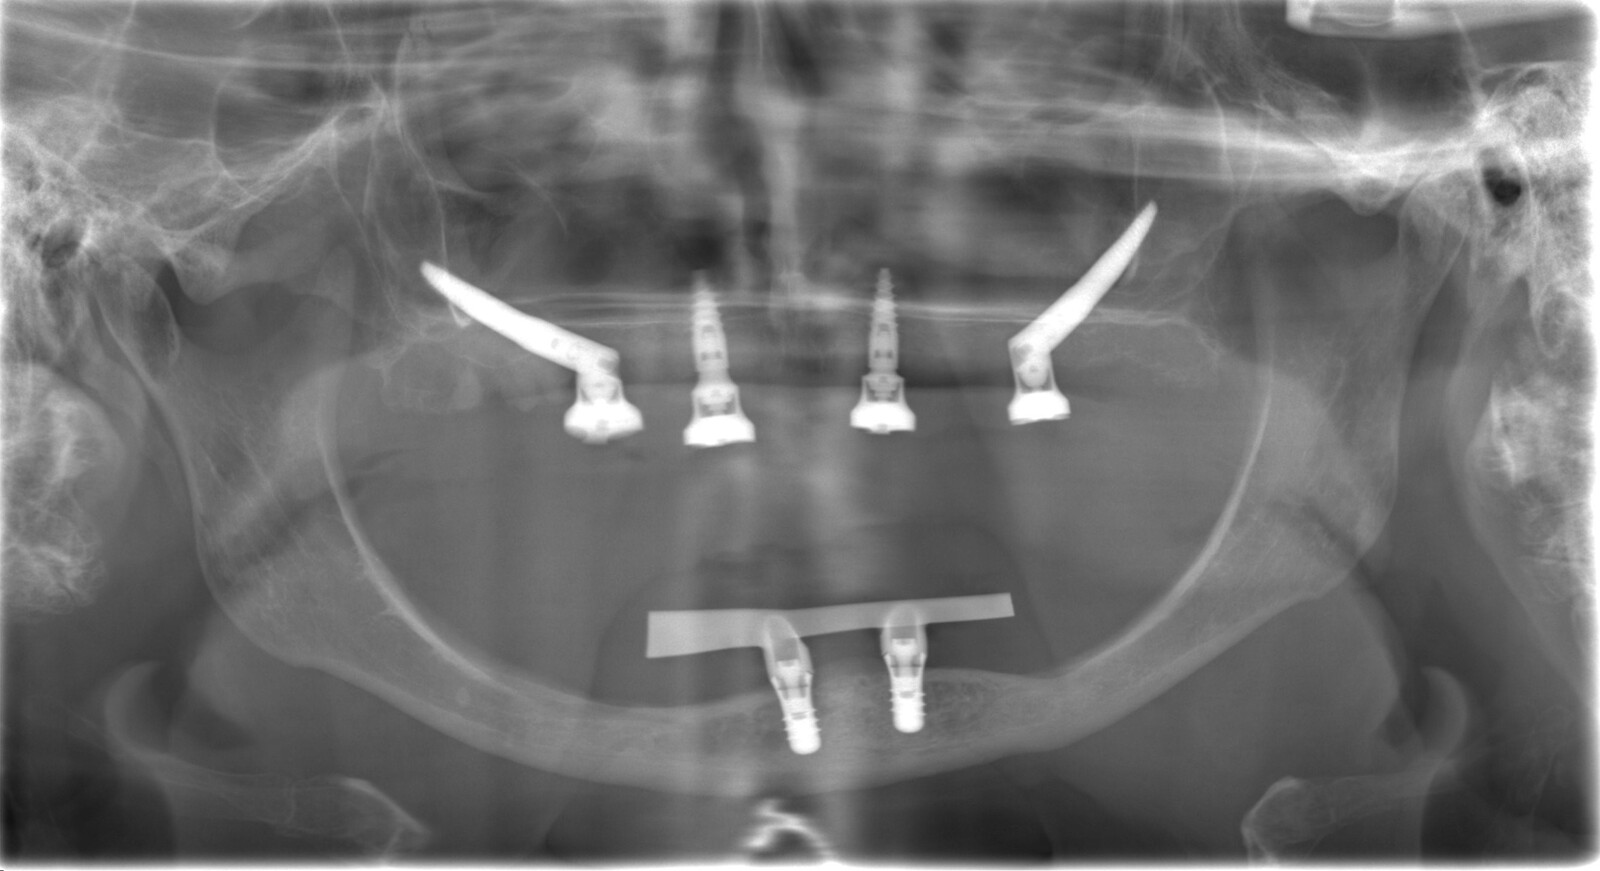

Een 80-jarige patiënte, bekend met gebruik van bloedverdunners, presenteerde zich met functionele en esthetische klachten door volledig uitneembare prothesen in boven- en onderkaak die zij al >40 jaar droeg. De prothesetanden waren sterk versleten en zowel retentie als stabiliteit was matig, wat leidde tot kauwproblemen en verminderd comfort. Klinisch en radiologisch werd een zeer ernstige resorptie vastgesteld in zowel de maxilla als de mandibula, passend bij Cawood & Howell-classificatie V–VI (figuur 9-11).

Preoperatieve situatie op een OPT.

Postoperatieve CBCT-scan.

Postoperatieve OPT.